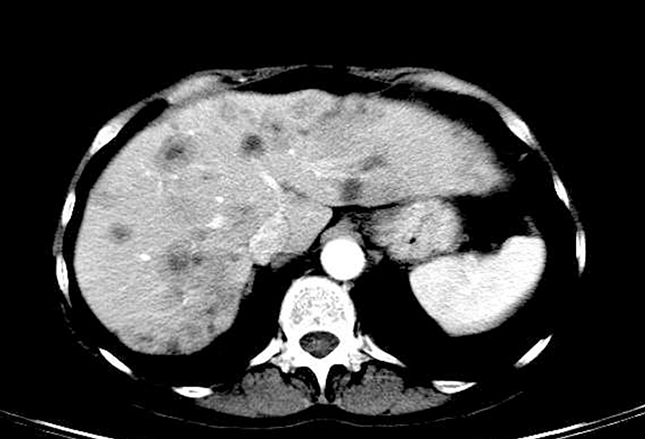

上图为SCLC患者对比增强CT扫描,显示出肝脏无数低密度病变。综合考虑SCLC病史、肝脏低密度病变及肝脏病变边缘模糊,该患者很可能发生SCLC转移。